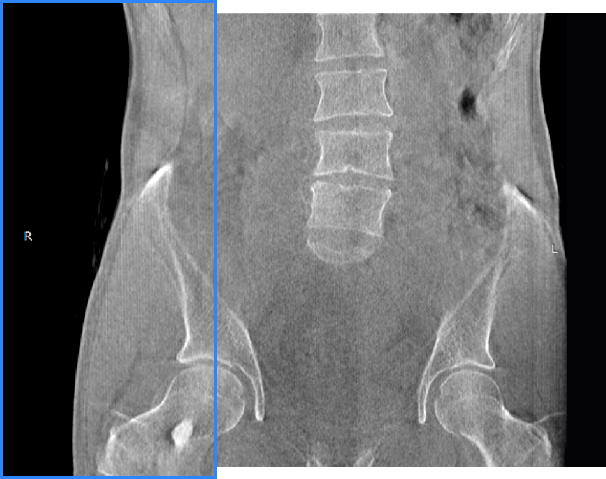

• 髋关节

支持双腿或双侧髋关节扫描 | 方便对比,降低漏诊误诊

FOV 250mm

FOV 350mm